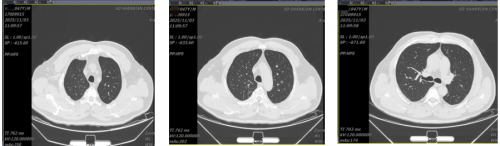

11月3日复查胸部CT:肺内感染治疗后复查所见,较前呈吸收好转改变;双肺纤维灶、微小结节灶。